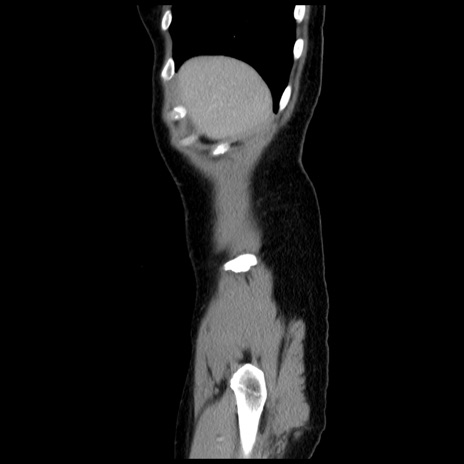

横断像

冠状断像